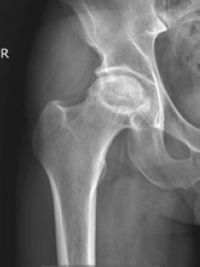

随之而来的问题是小段经常觉得髋部疼痛,逐渐出现行走困难,最近到西南医科大学附属中医医院骨伤科关节·足踝组就诊,被确诊为“酒精性股骨头缺血性坏死”。

入院后,骨伤科关节·足踝组郝琦为小段做了详细检查,发现他的股骨头缺血性坏死已经到达III期,必须要通过手术清除死骨,解除骨内压力和改善血供,坏死区域支撑防塌陷。

经讨论,决定采用“钻孔减压+陶瓷骨棒支撑治疗”股骨头缺血坏死,即在彻底清理死骨的基础上,在坏死区域植入生长颗粒,“多孔生物陶瓷棒”支撑和引导血管长入的作用,以期望重建骨坏死血供,最终植入的陶瓷棒被自体骨逐渐成骨替换,待自体骨替代后最终实现永久性生物支撑。

酒精性股骨头坏死多由大量饮酒、药物导致股骨头的血液循环障碍,继而发生软骨下骨折、关节面塌陷、关节功能障碍等一系列病理改变,从而导致髋部疼痛、功能障碍。